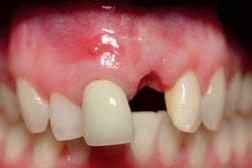

60 Top Dentists 2025

The annual Top Dentist list showcases excellence in dental care. See which New Hampshire dentists were voted by their peers as the most trustworthy.